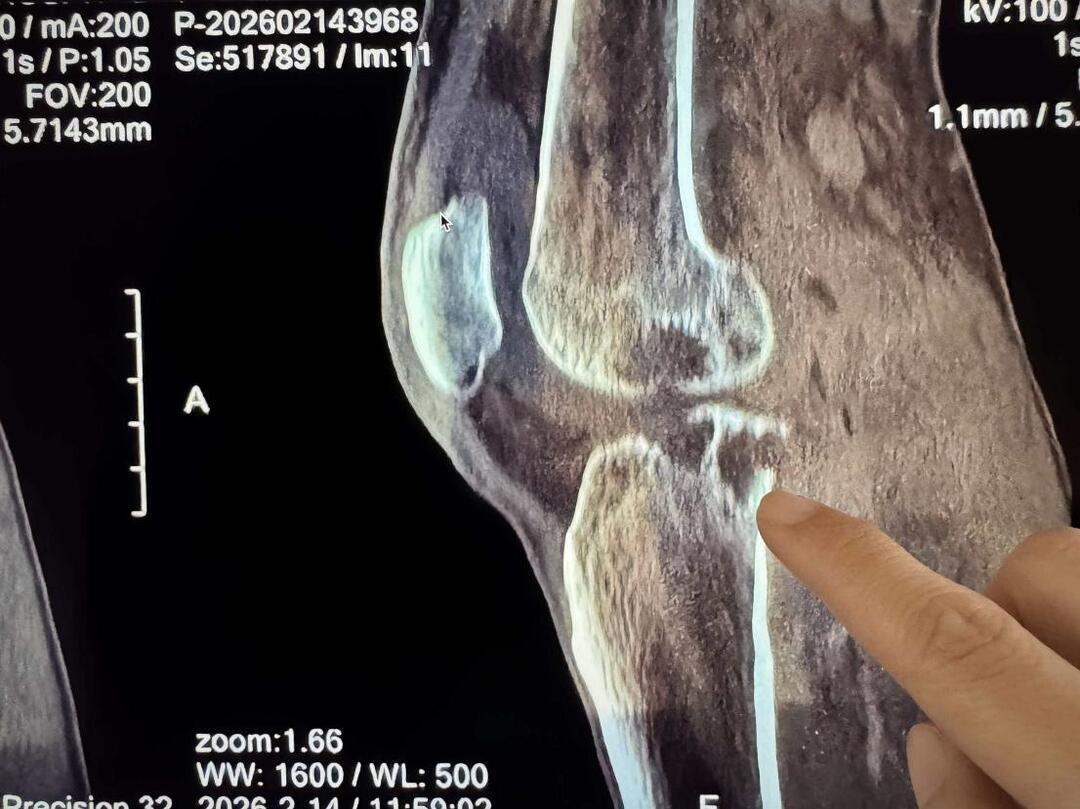

诊断的难点在于结核病的隐匿性。在资源相对匮乏的环境下,医疗队专家围在诊室窗前,利用自然光线反复研判CT影像。放射科陈娟医生结合患者影像学特征,精准捕捉到了骨质破坏的细微病灶;感染科周宁医生则从实验室检查结果入手,深入分析患者全身情况;骨科黄先哲医生通过详细体格检查,评估其膝关节功能受损程度。

经过多轮综合研判,专家组排除了痛风、肿瘤等疑似疾病,最终锁定真凶——“右膝关节结核”。若不及时规范化治疗,该患者将面临终身残疾。

确诊后,诊疗小组立即为患者制定了个性化的抗结核治疗方案。诊室内,中国专家对着胶片,并结合该病例,现场为当地医生及其他医务人员开展专题培训,详细讲解膝关节结核的临床表现、诊断要点及规范治疗流程。冀其通过“床旁带教、手把手指导”的方式,助力提升塞方医生的本土抗结核水平。